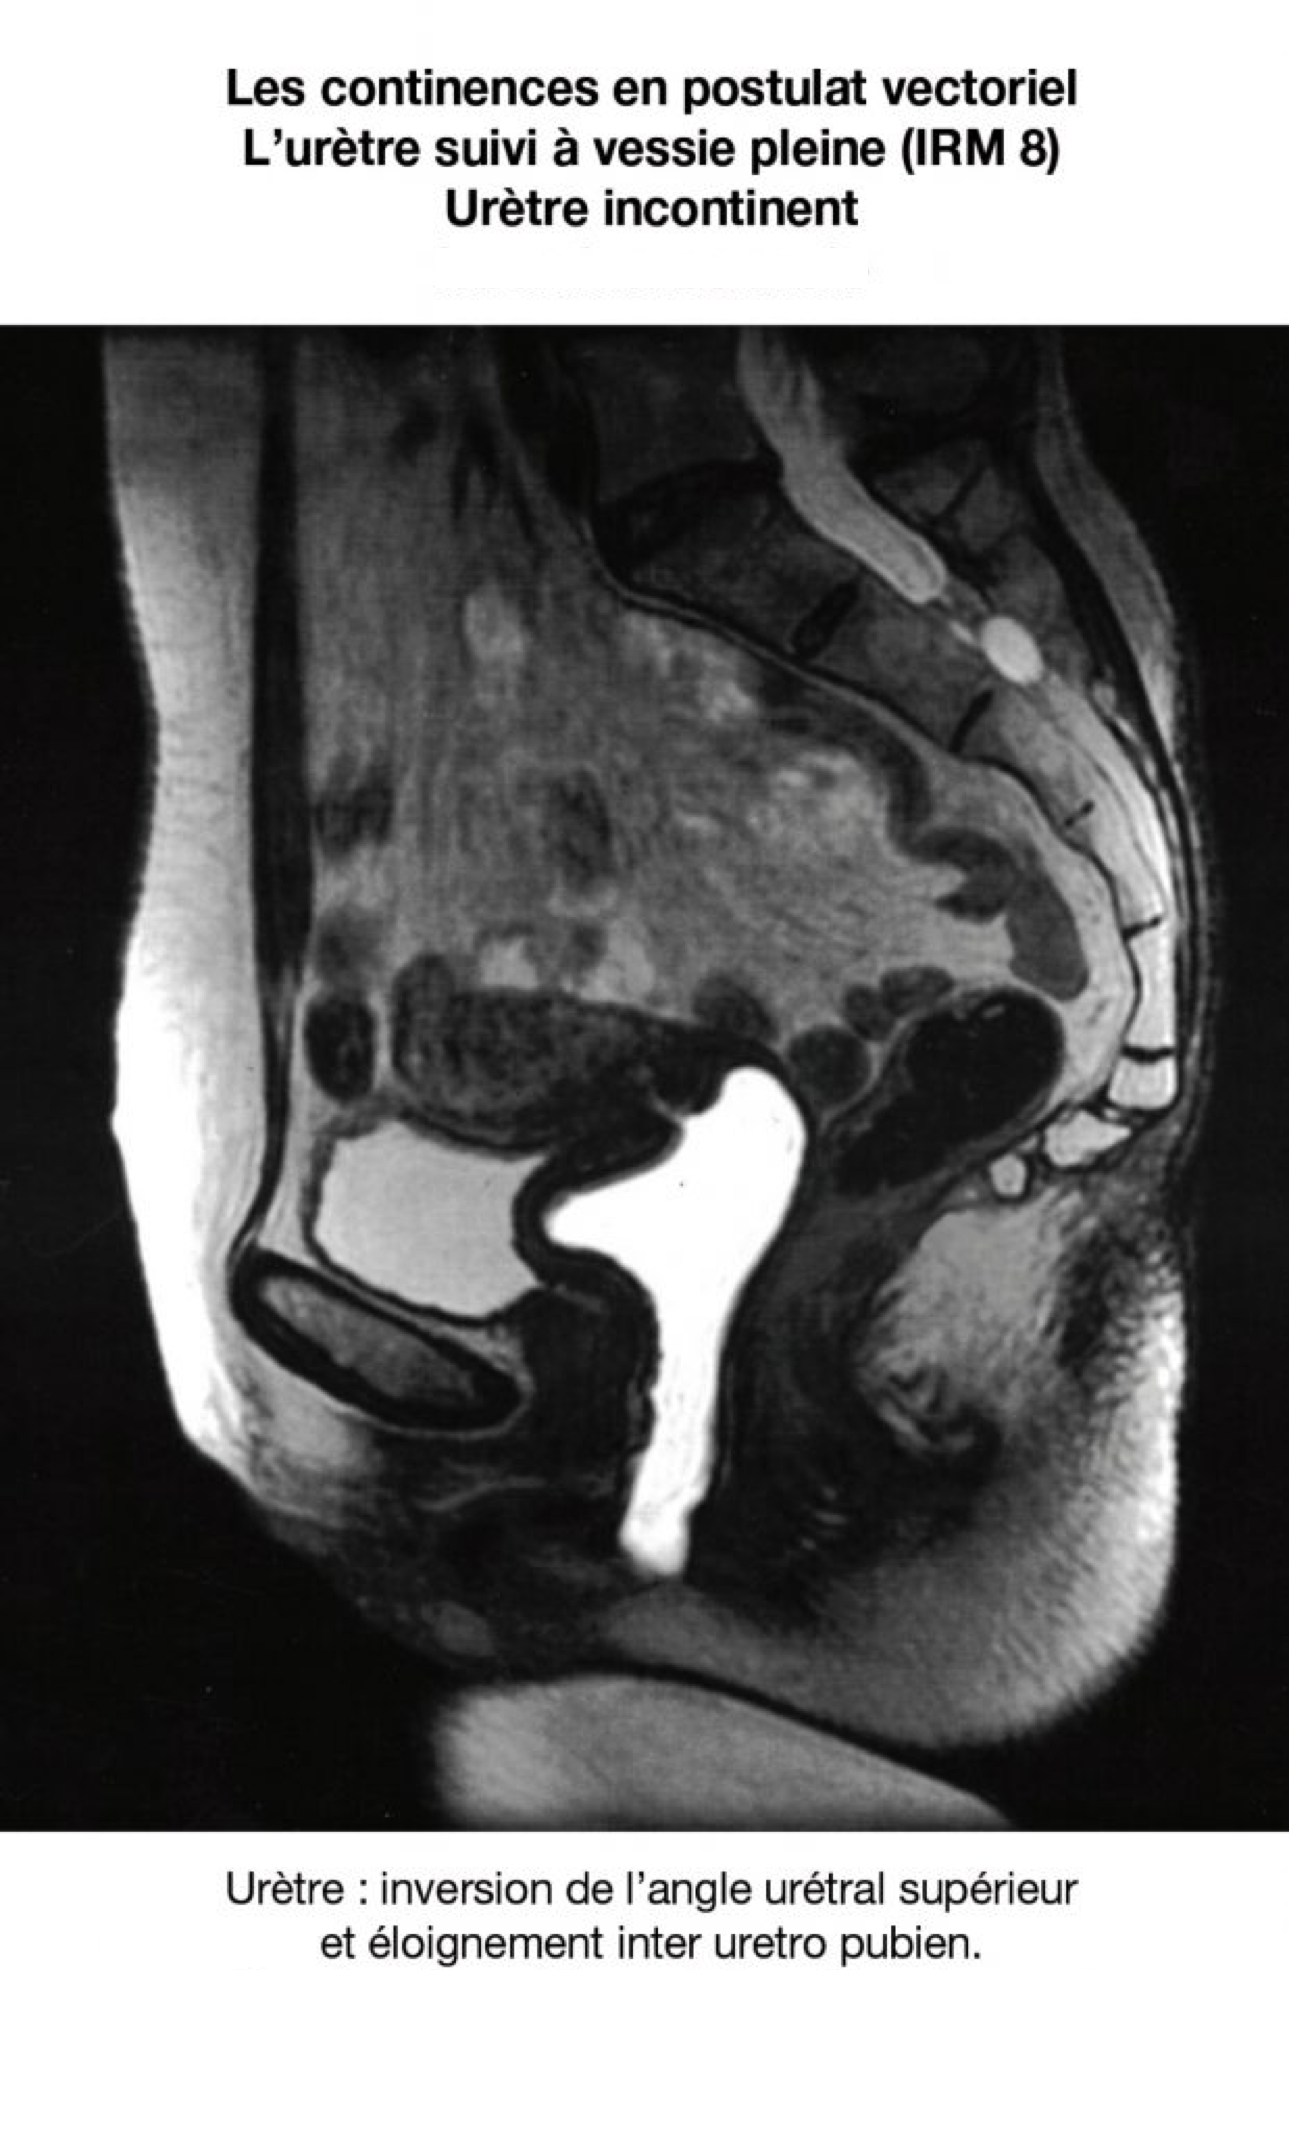

En postulat vectoriel, leur rôle essentiel pourrait être (???) celui de propriocepteurs ; et ils accentueraient et participeraient aux effets de clôture lors des glissements du tissu visco élastique pelvien. Divers arguments plaident en faveur de ces hypothèses : Pour l’urètre : 25% des vessies sont continentes à sphincter ouvert (ref 5). L’urètre continent de l’IRM n’est pas rectiligne. Il décrit un trajet en zigzag et la distance uretro pubienne faible. (Sa plicature peut être un mécanisme de continence). L’urètre continent n’est rectiligne que lors de l’incontinence physiologique, la miction (uretrographie mictionnelle).

14. Le zigzag urétral

EN CAS D’INCONTINENCE, L'URÈTRE NE DÉCRIT PLUS UN ZIGZAG OCCLUSIF.

IL EST RECTILIGNE OU CONCAVE EN AVANT AVEC DISTANCE PUBO URÉTRALE AUGMENTÉE